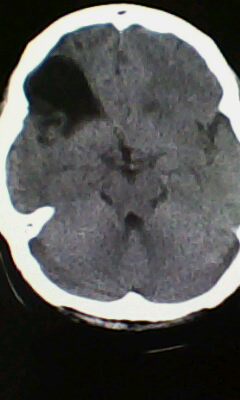

标题: CT25171:患者间断性头痛 无外伤史 [打印本页]

标题: CT25171:患者间断性头痛 无外伤史

右侧额叶脑穿通畸形囊肿。

图不清,有灰质异位吗?与脑裂畸形鉴别

右侧额叶脑穿通畸形囊肿。支持!